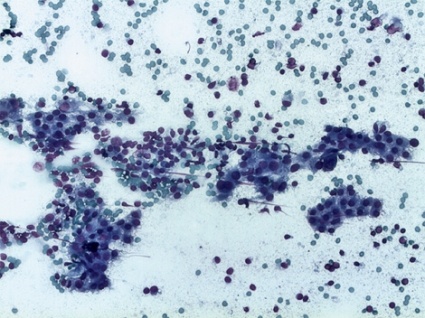

Den på våra breddgrader helt dominerande orsaken till sköldkörtelproblem är autoimmunitet;därom råder allmän enighet. Ett sätt att specifikt dokumentera autoimmunitet riktad mot sköldkörteln är att undersöka sköldkörtelvävnad med avseende på förekomst av lymfocytär invasion. Sådan undersökning görs med finnålscytologisk (FNA) teknik. Vi har i Sverige erkänt hög kompetens inom detta område [2, 3]. Värde och tillförlitlighet av FNA som robust och riskfri undersökning, även under primitiva betingelser, har helt nyligen bekräftats [3].

Genom att fördjupa diagnostiken av tyreoidea med tillägg av FNA som komplement till sedvanliga biokemiska och serologiska prov har vi visat att autoimmunt angrepp på sköldkörteln kan dokumenteras hos patienter med misstänkt tyreoideasjukdom i långt större utsträckning än om utredningen innefattat enbart biokemiska och serologiska prov [4]. Hos ungefär hälften av patienterna med symtomgivande autoimmun tyreoidit var förstahandsprovet TSH inom laboratoriets referensområde, ett tillstånd där vi föreslagit beteckningen subkemisk hypotyreos [5].